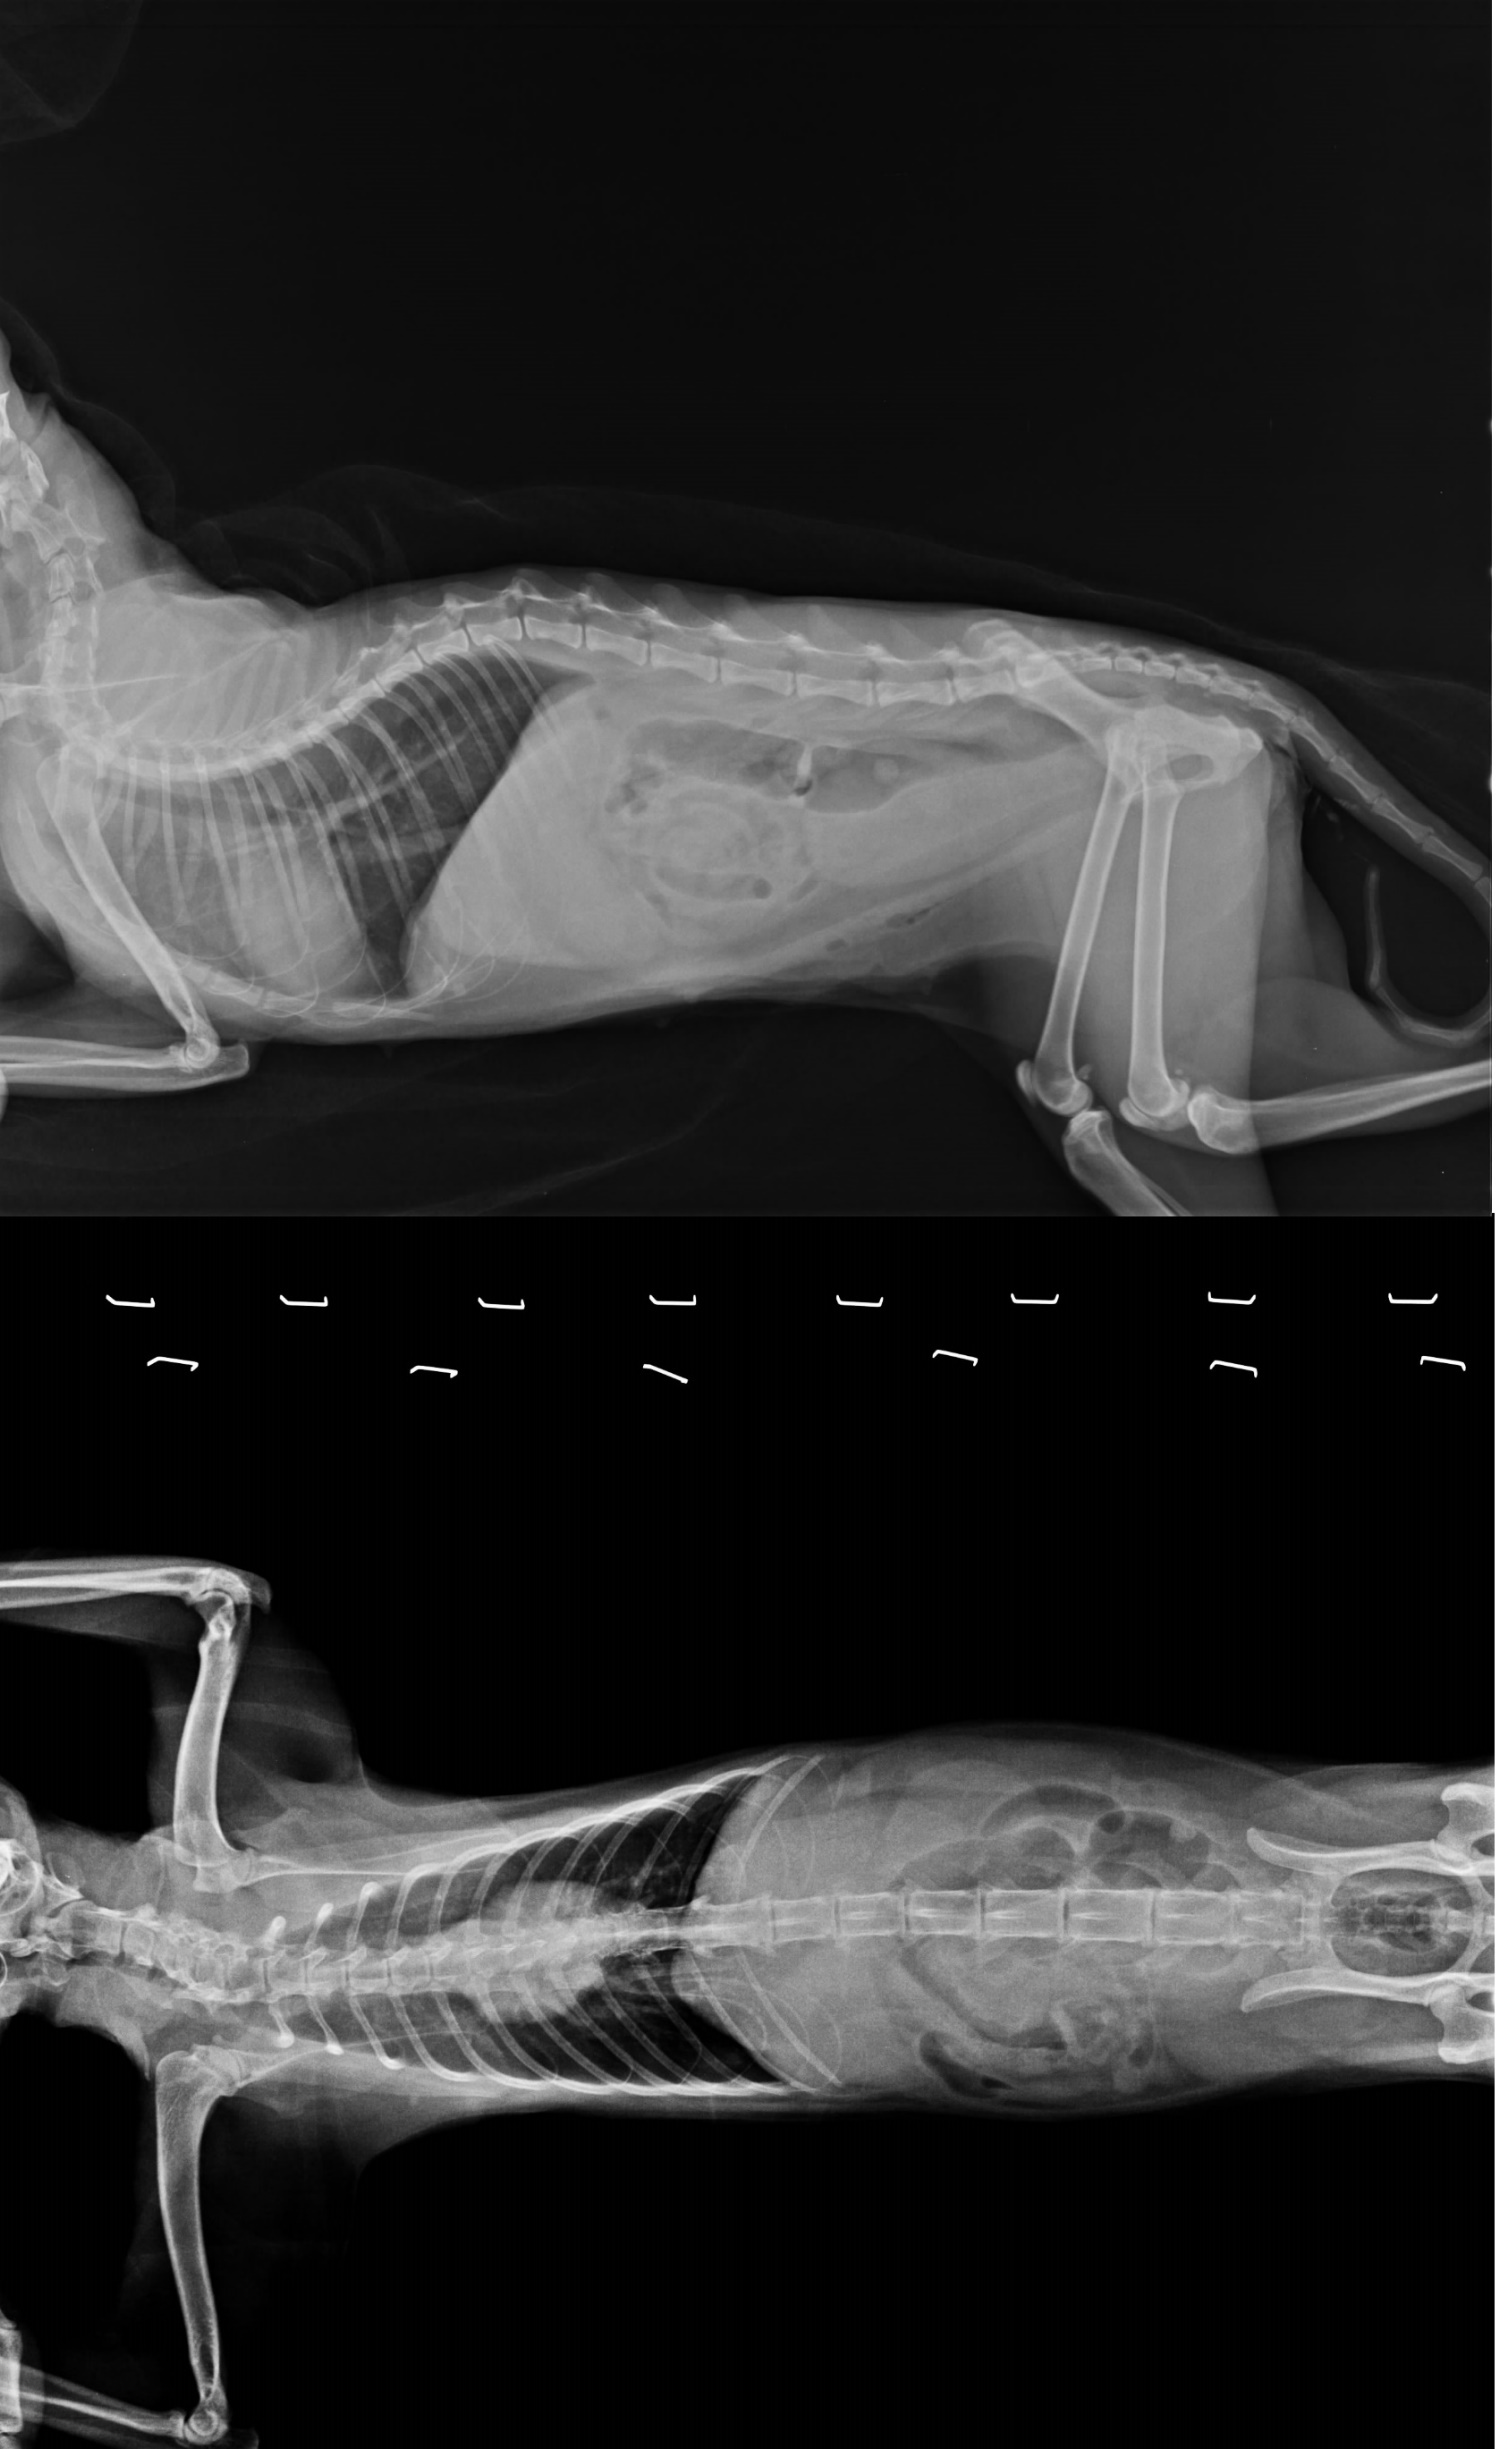

志工於收容所帶出一批即將面臨安樂的成貓,送醫結紮發現貓咪子宮蓄膿嚴重,白血球五萬多,施打抗生素三天不見改善,不吃不喝又爆發嚴重鼻氣管炎,張口呼吸,眼鼻分泌物很多,慘不忍睹,緊急轉院至24小時看護的醫院,除給予皮下點滴外,早晚噴霧,嚴密監控發炎指數,換過幾種抗生素,狀況才得以控制,但貓咪始終不願意自己進食,全賴醫師灌食,經過三十天,貓咪開始願意舔灌頭,食慾慢慢增加,一天比一天好,也願意吃一點小飼料,慢慢的幾乎天天都吃光光,等食慾胃口正常已先帶回協會安置。